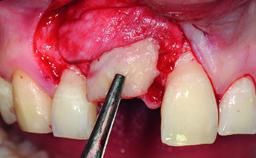

Replacement of a Missing Upper Left Central Incisor, Late Placement of an RC Bone Level Implant and Adjacent Tooth Restoration

A healthy 38-year-old male patient was referred for replacement of a failing tooth-supported cantilever fixed dental prosthesis on teeth 11 and 21. The patient reported a history of trauma at 13 years of age that had resulted in the subsequent loss of tooth 11, as well as endodontic treatment of the adjacent abutment tooth 21. A metal-ceramic cantilever fixed dental prosthesis replacing tooth 11 had been provided by his general dentist several years after the loss of the tooth, with tooth 21 as the sole abutment. At the time of initial presentation, this restoration had been in service for over 20 years.